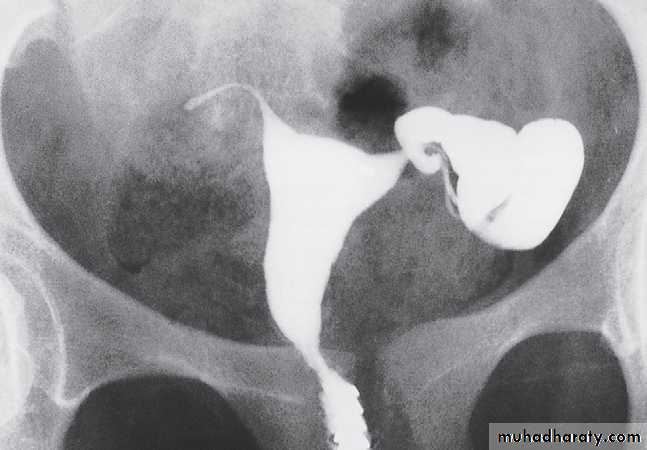

The lost intrauterine contraceptive device (IUCD) is a relatively common problem and ultrasound should be the first investigation. Different devices have characteristic appearances. They are seen as highly reflective structures and their relationship to the uterine cavity can be determined.Hysterosalpingography is a contast study of uterus & both fallopian tube used to investigate selected cases ofinfertility in order to assess the patency of the fallopian tubes. A catheter with a seal to prevent leakage from the external cervical os is inserted into the uterus. Sufficient iodinated contrast is then injected under fluoroscopic control to fill the uterus and fallopian tubes .

If the fallopian tubes are patent, there is free spill into the peritoneum, recognized by the demonstration of contrast between loops of bowel. Congenital variations in uterine morphology, which may prevent maintenance of pregnancy, can also be assessed.

Ultrasound hysterosalpingography may be performed to detect tubal patency. This technique, which avoids the use of ionizing radiation, involves injecting an ultrasound contrast agent into the uterus through a catheter and following the passage of contrast through the fallopian tubes with ultrasound.